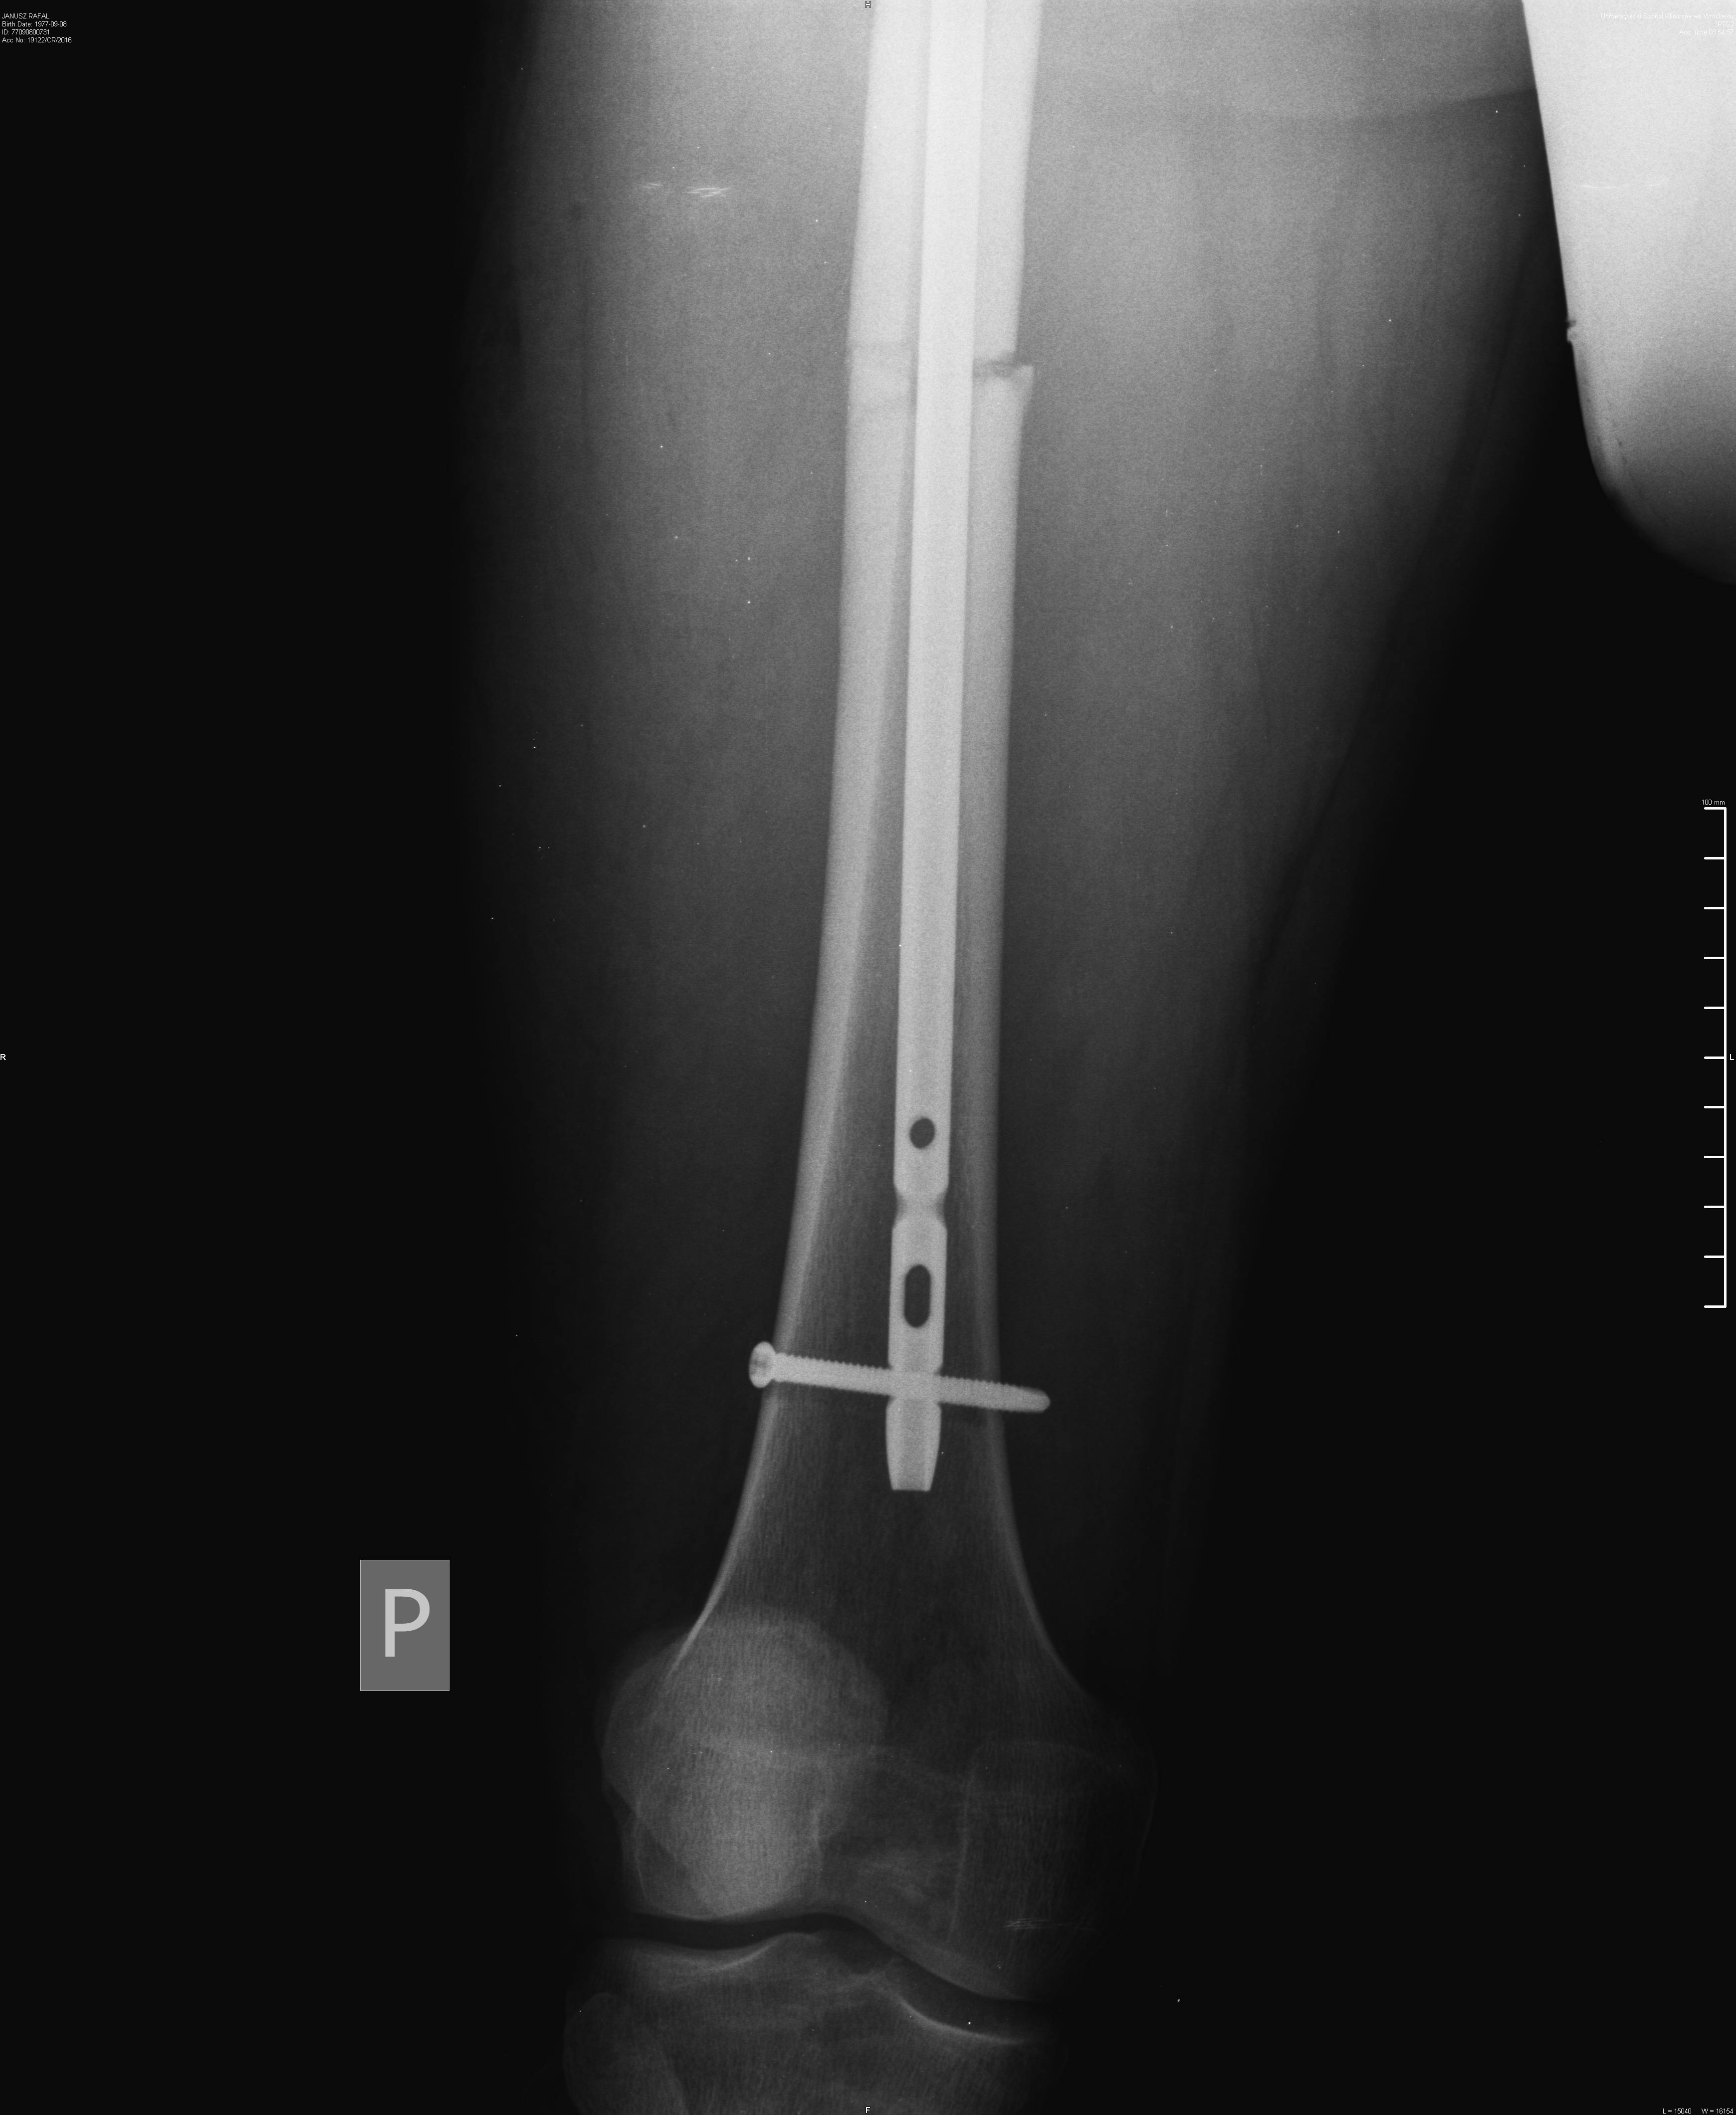

Wklejam bo może ktoś jeszcze nie miał nic złamanego i jest ciekawy jak to wygląda.

Terminator Rafał . Ale widzę że już się zrasta.

Bramki na lotnisku będą ci teraz piszczały